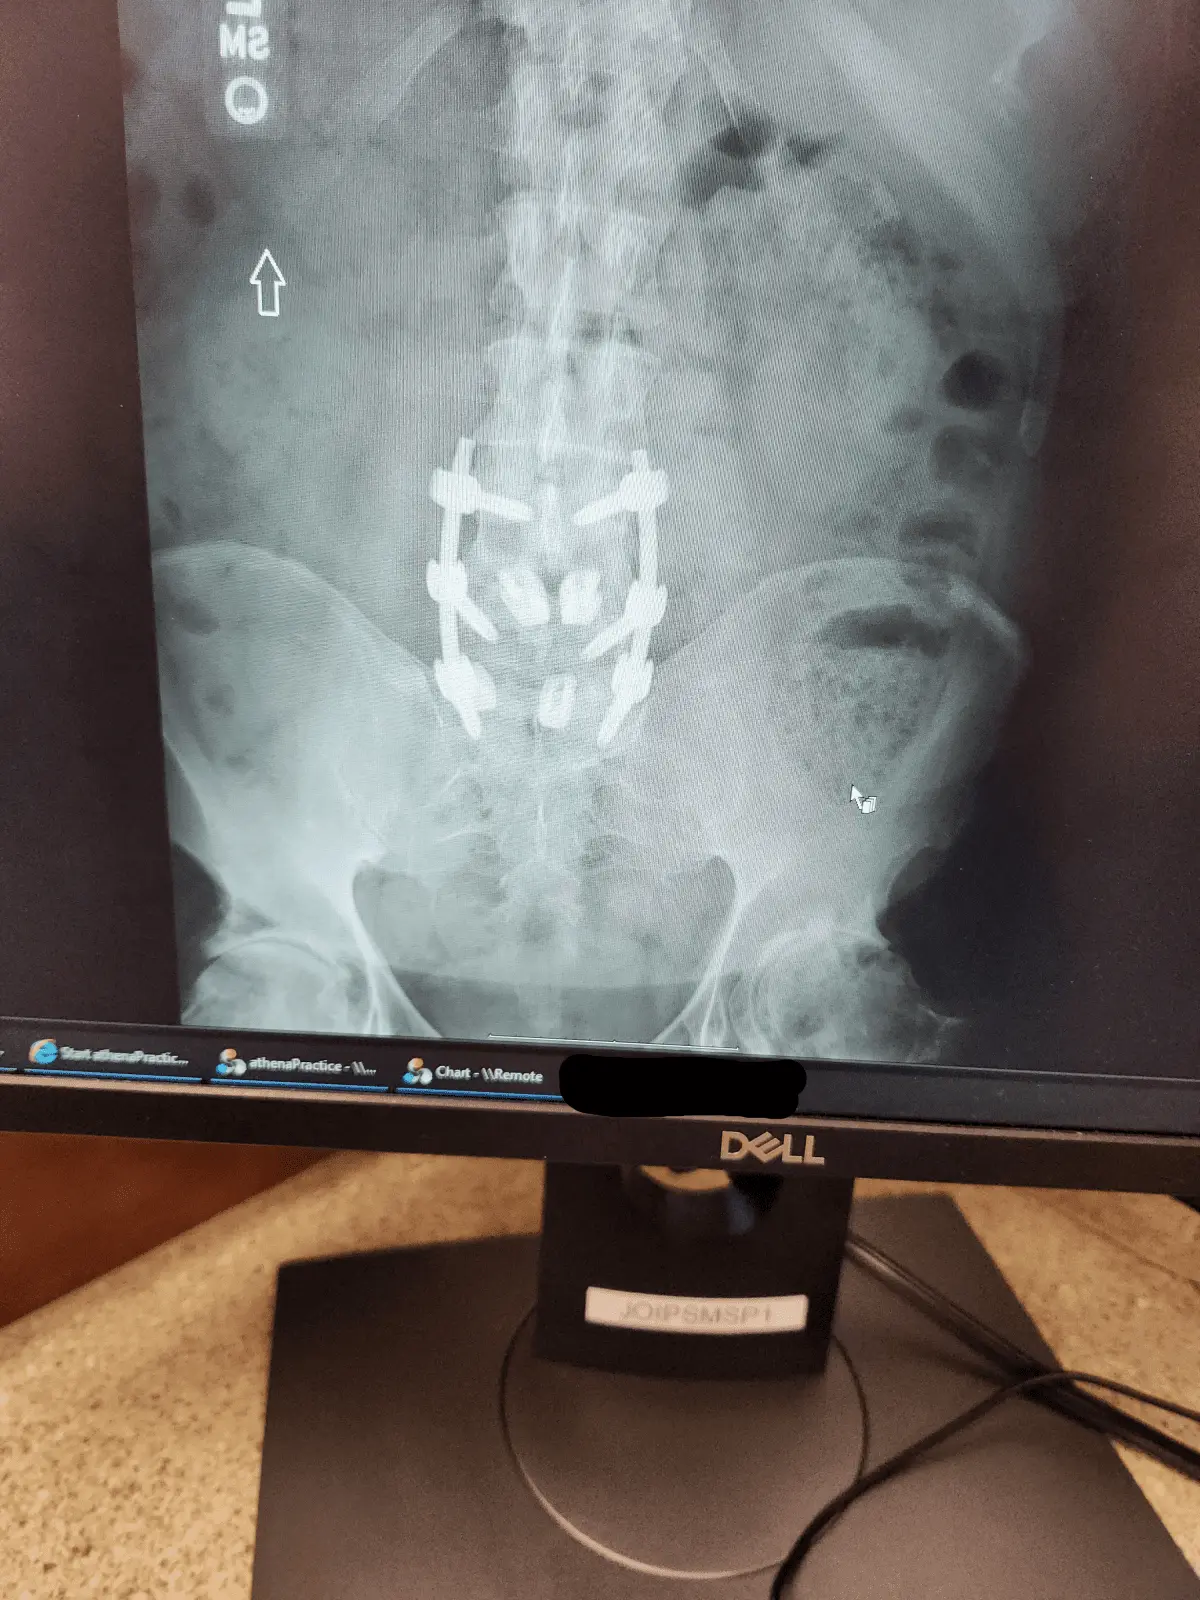

He said my bones hsve fully fused

He says it’s muscular knots in the connection tissue and I need months of professional stretching and massage

My fusion did not require a cage !!

I only got 2 huge spacers